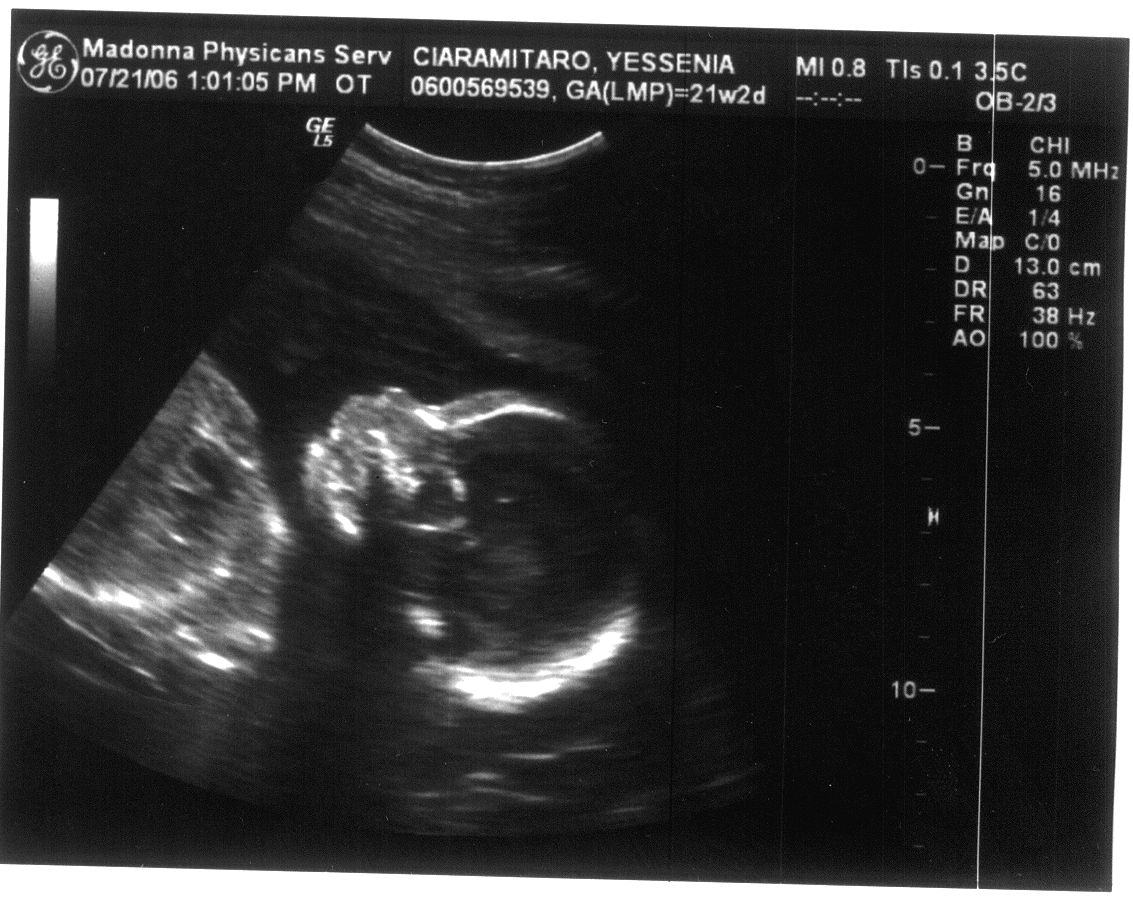

Last Modified On:March 2, 2015 5 PM Welcome to the future member of the Ciaramitaro clan!

Looks like our baby is coming bundled with a Skeleton Halloween Costume!